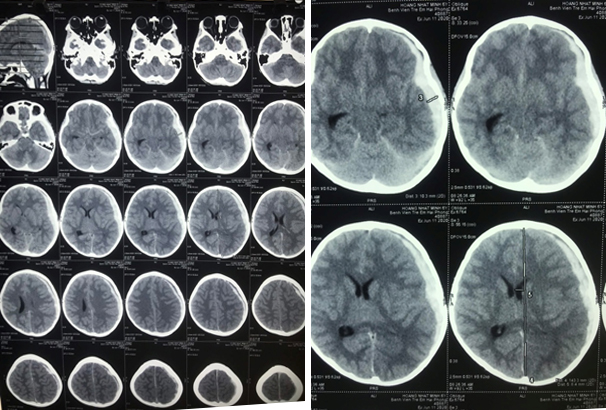

Sau khi chụp phim CT Scan sọ não phát hiện khối máu tụ dưới màng cứng vùng trán, thái dương, đỉnh trái có đè đẩy đường giữa qua phải 8,4mm, gây xẹp não thất bên trái.

Phim CT Scan sọ não khi nhập viện

Phim CT Scan sọ não sau mổ